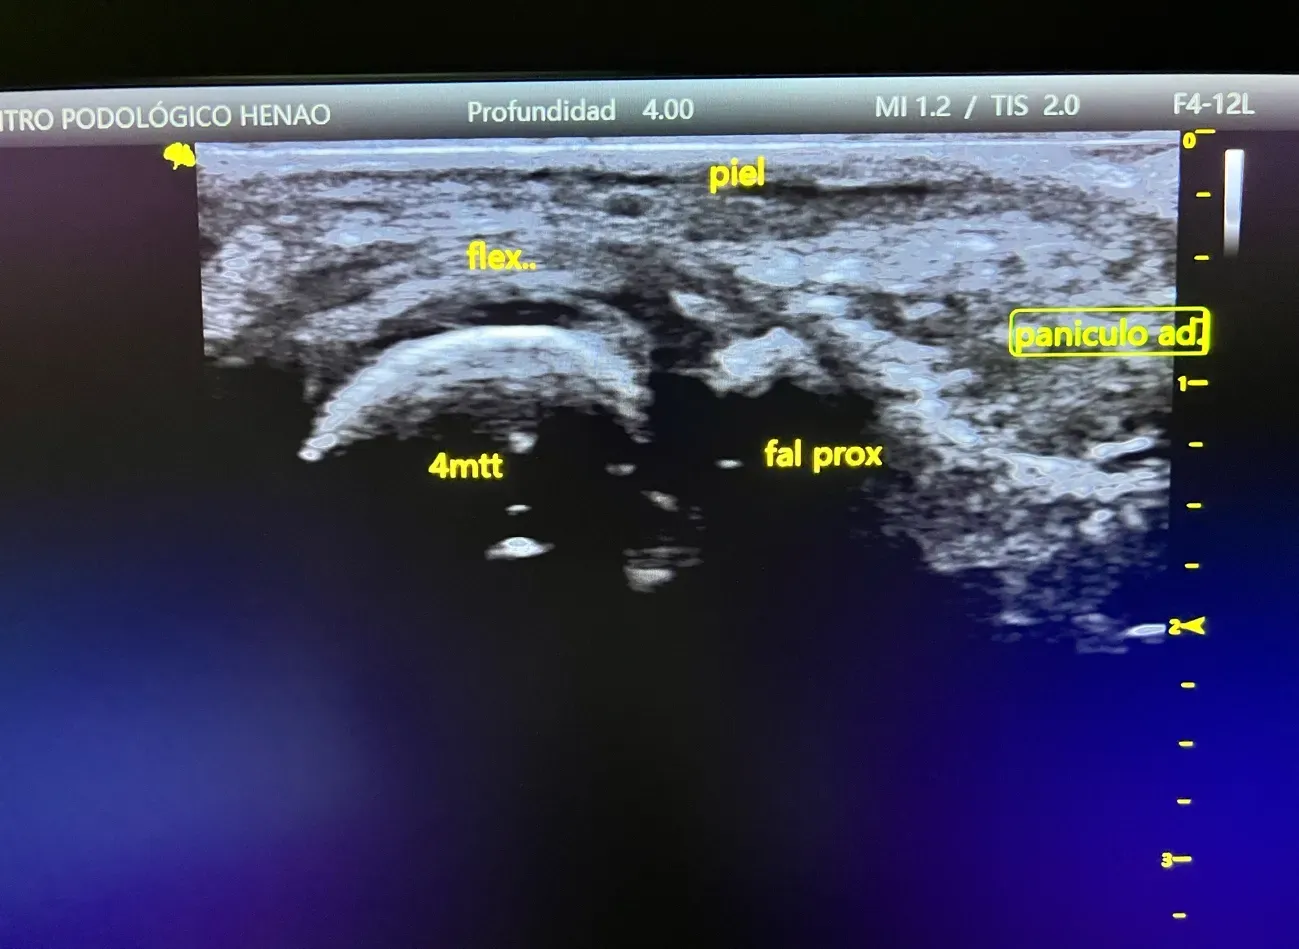

Metatarsalgia y Dolor en Antepié

El dolor en la parte anterior del pie es muy frecuente en diabéticos. Se debe a alteraciones en el reparto de cargas al caminar, atrofia de la almohadilla grasa plantar y cambios biomecánicos. Puede causar dificultad para caminar y afectar la calidad de vida.

Metatarsalgia y Diabetes: Por Qué Es Tan Frecuente

La metatarsalgia es el dolor localizado en la parte anterior del pie, en la zona de los metatarsianos. En pacientes con diabetes es especialmente frecuente por varios motivos:

- Alteraciones en el reparto de cargas al caminar

- Atrofia del panículo adiposo plantar: la almohadilla grasa que protege el antepié se reduce

- Cambios en la movilidad del pie y del tobillo

★ Ecografía Podológica Estrella

Diagnóstico ecográfico avanzado de lesiones del pie y tobillo sin dolor ni radiación.